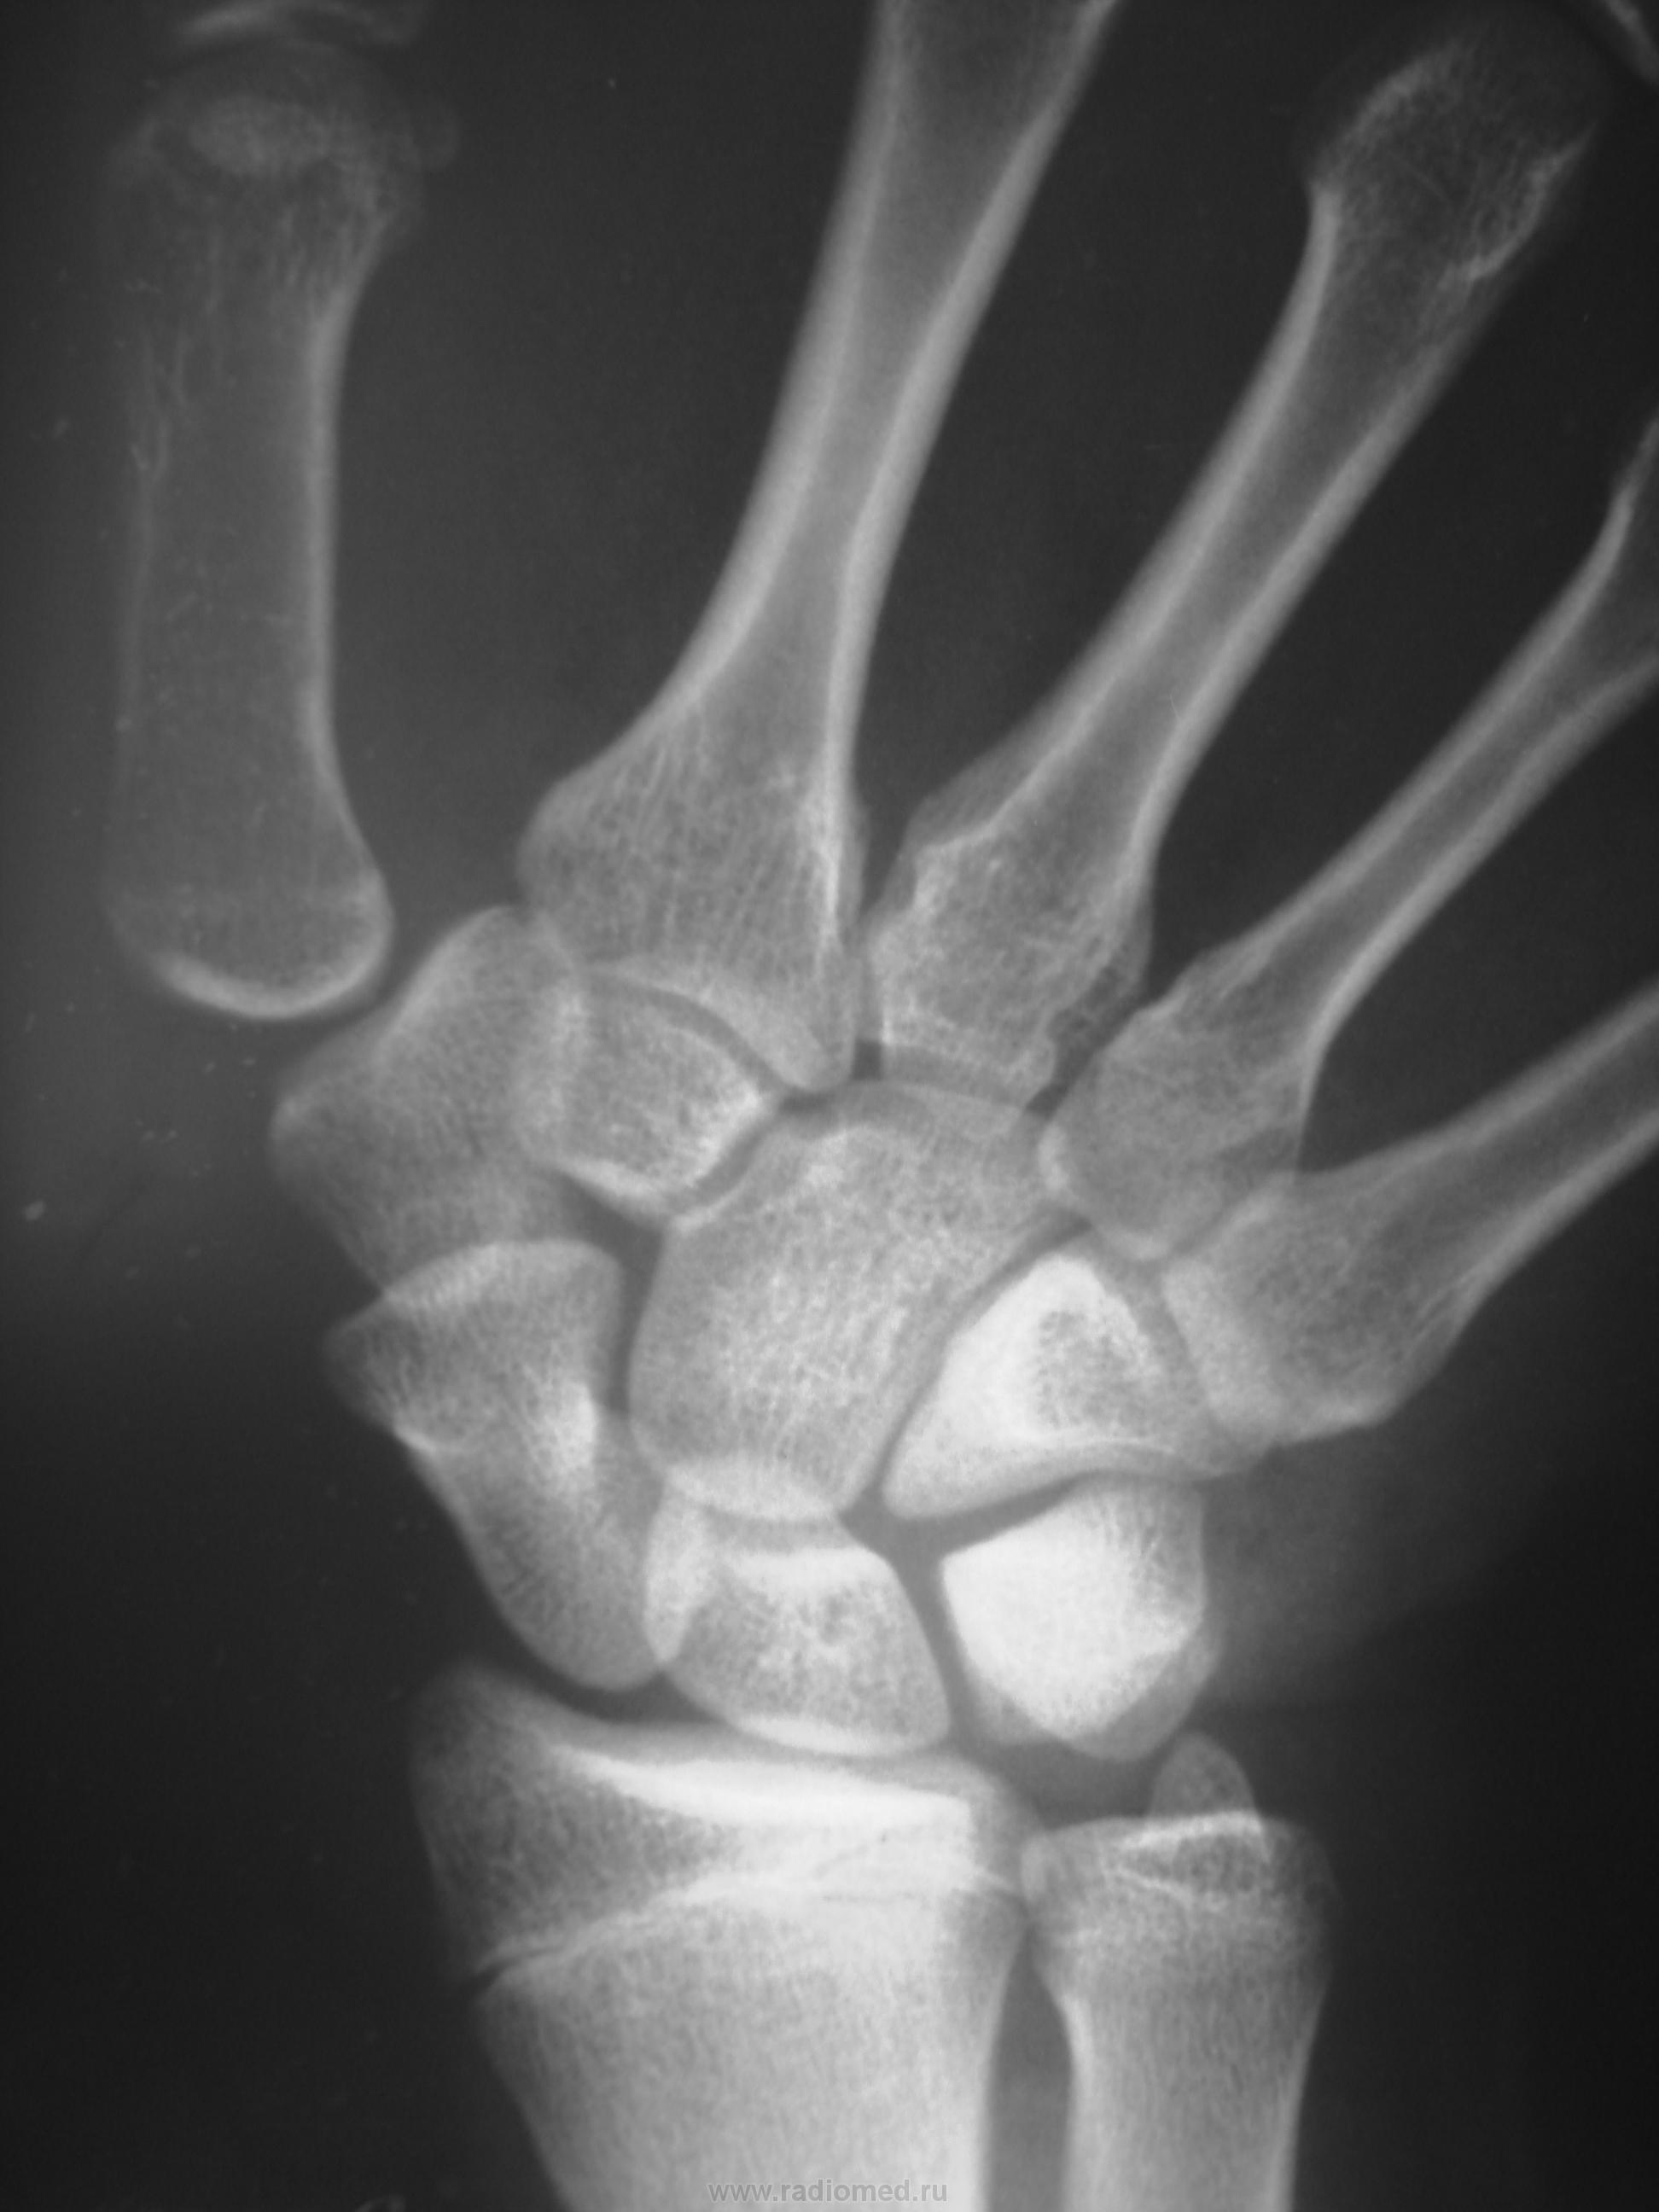

Травма в октябре 2009,сейчас появились боль, припухлость в обл. ладьевидной кости. Какие будут мнения, уважаемые коллеги?

Значит в октябре не болело. Это странно. Несросшийся перелом есть. А вот псевдартроз как-то не очень... Здесь нужна проекция для ладьевидной кости, без наслоений других.

В  октябре само сабой болело,перелом был диагносцирован,ходил в гипсе, но через месяц сняли и носили ортез. Не болело до настоящего времени.

В наших условиях - знатоки говорят о необходимости операции чуть ли не в первые 2 часа после перелома, переломы ладьи никогда не срастаются...